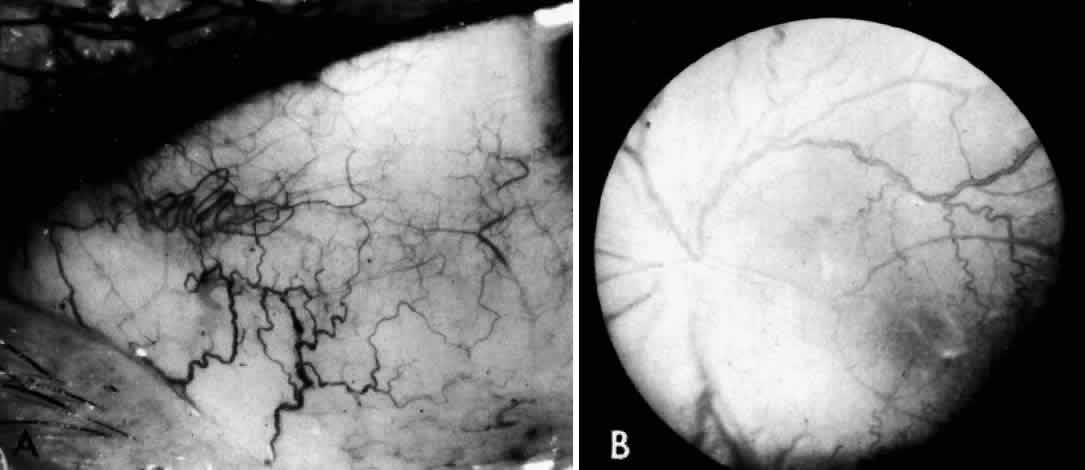

Electron microscopic examination of the cornea and retina showed the lipid stored was in the form of membranous cytoplasmic bodies (Fig. 7).68 The distribution of these inclusion bodies is similar to that of the birefringent material seen on light microscopy. The bodies are most abundant in retinal ganglion cells and retinal pigment epithelium. They are present in moderate numbers in corneal stromal cells, lens epithelium, corneal endothelium, vascular endothelium, and the sphincter muscle of the iris. They are infrequent in Müller cells, glial cells, and rod and cone inner segments.

Fig. 7. Retinal ganglion cell. (A) Portion of cell in Niemann-Pick disease, showing numerous membranous cytoplasmic bodies. Mitochondria (m) and dilated endoplasmic reticulum (er) are also evident. Area outlined in lower right is shown in greater magnification in B. (× 15,000) (B) Portion of cytoplasm of ganglion cell shown in A. Membranous cytoplasmic bodies cut in several different planes are evident, as are mitochondria (m) and endoplasmic reticulum (er) (×42,000). (Robb RM, Kuwabara T: The ocular pathology of type A Niemann-Pick disease: A light and electron microscopic study. Invest Ophthalmol 12:366, 1973)